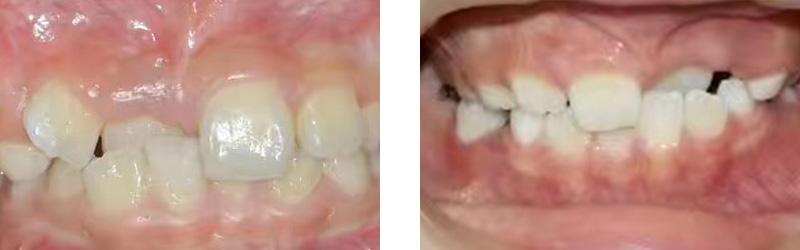

病例分享